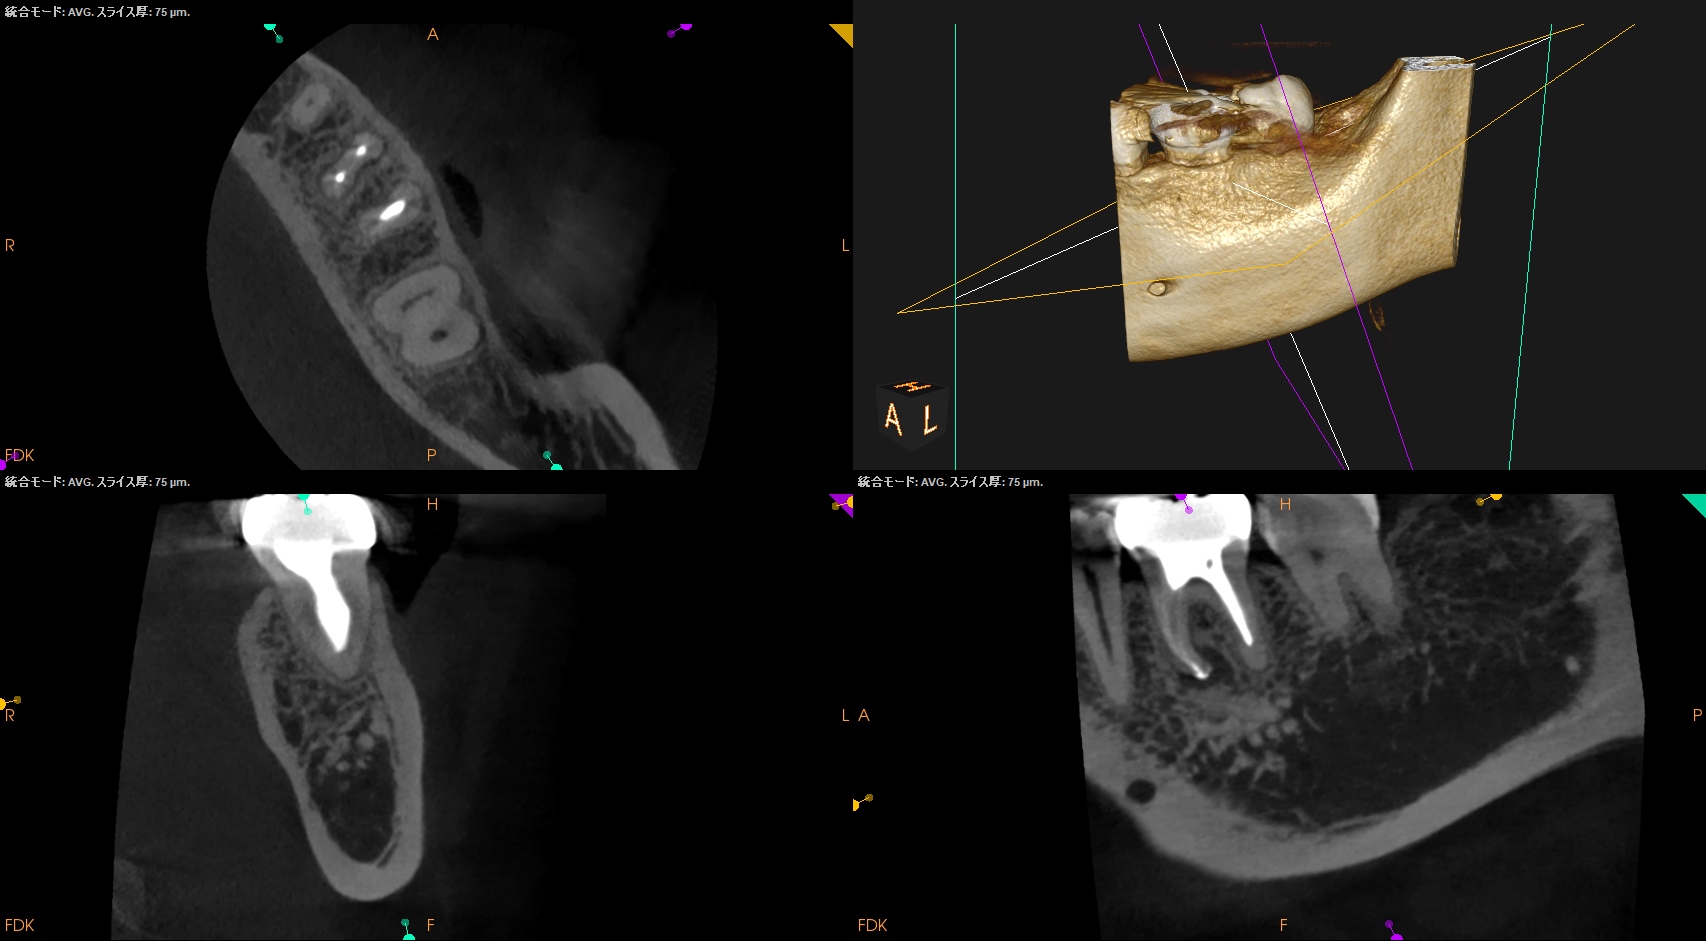

Post-op 1yr Endo test(2026.1.20)

術前の臨床症状は消失した。

外科の切開線の痕もない。

まさに完治だ。

術後の骨欠損は完治した。

ということで経過観察も終了である。